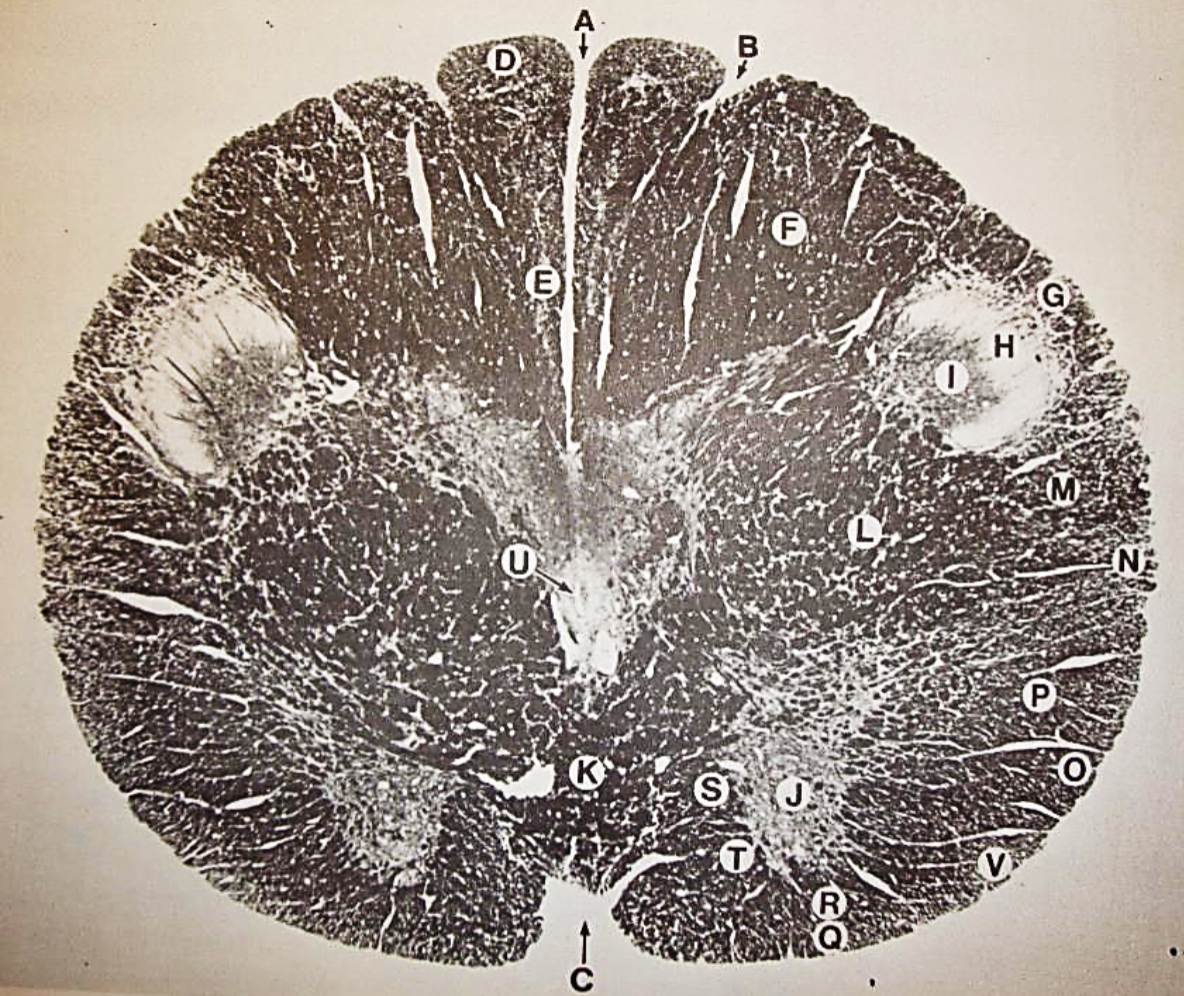

A

Fasciculus gracilis

B

gracile nucleus

C

fasciculus cuneatus

D

cuneate nucleus

E

spinal trigeminal tract

F+G collectively

spinal trigeminal nucleus

H

accessory nucleus

I

pyramidal decussation

J

rubrospinal tract

K

posterior spinocerebellar tract

L

anterior spinocerebellar tract

M

lateral spinothalamic tract

N

anterior spinothalamic tract

O

lateral vestibulospinal tract

P

medial longitudinal fasciculus

Q

tectospinal tract